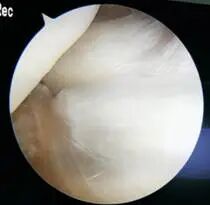

治疗关节囊肿的方法包括保守治疗和手术治疗。保守治疗包括使用非甾体类抗炎药、物理治疗和囊肿抽液等。手术治疗通常是在囊肿较大或症状严重的情况下进行,包括关节镜下囊肿切除和开放性手术切除等。传统的开放式手术:具有疤痕大、影响关节功能,由于没有处理膝关节腔内病变及后方关节囊的裂隙样结构,囊肿相对容易复发,病人恢复缓慢等缺点。关节镜手术可以做到切口小、恢复快,同时可以做到“标本兼治”,复发率低。如下图所示:

关节镜治疗腘窝囊肿方式有多种,常见的关节镜手术方式有:①囊外切除—双后入路,一般用于原发型囊肿;②后关节囊裂隙样结构缝合;③囊内切除—前外侧入路结合单后内侧入路;④囊内切除—双后内侧入路囊内切除术。

选择何种方式可依据术前核磁共振的检查情况决定。核磁共振显示腘窝囊肿与关节腔相通,腓肠肌间隔血管、神经的囊肿时建议的手术方式为前内外侧入路处理膝关节腔病变+单后内或双后内入路切除囊肿。如下图所示:

对于如何选择单后内或双后内入路切除囊肿,一可以通过术前膝关节核磁共振的检查了解囊肿的大小、位置及是否存在分隔来决定;二可以通过术中视野及操作决定;由于单后内入路切除术,观察入路位于前方,由于胫骨平台及内侧腓肠肌的遮挡,视野存在一定的盲区,对于囊肿相对较小,基本位于膝关节线水平、无分隔的囊肿,可以选择该入路进行手术;而对于囊肿较大、囊肿上下边界距离关节线比较远的囊肿,为了较好的将囊壁较完全的切除通常选择双后内入路切除囊肿。